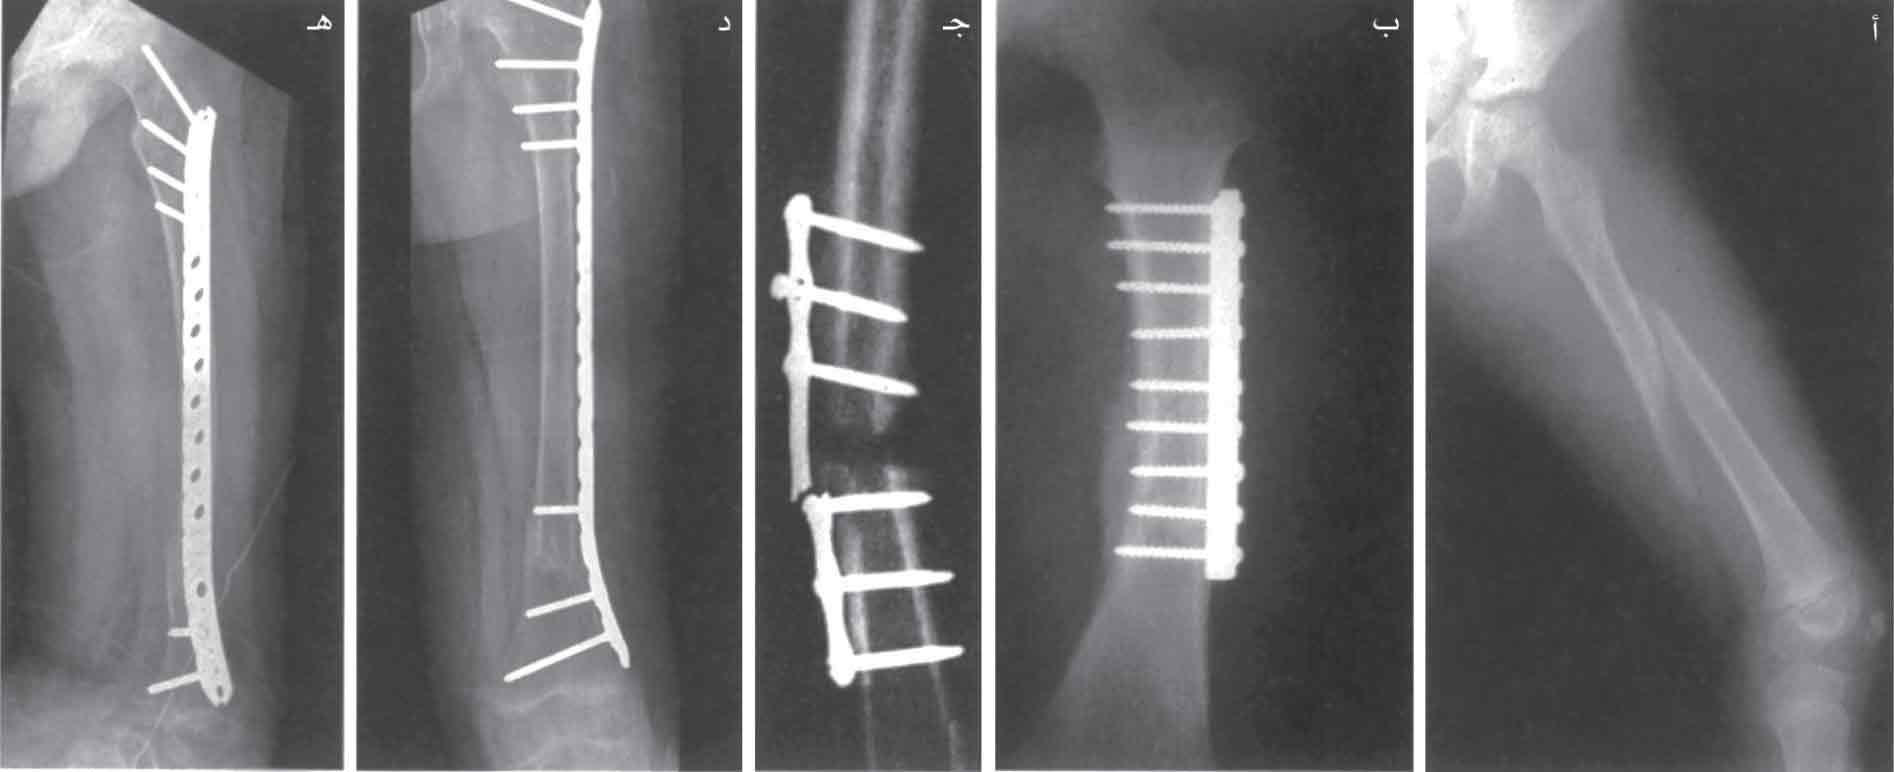

نماذج معالجة كسر تحت المدورين: أ- تثبيت بصفيحة ولولب بزاوية 90˚، ب- تثبيت بوساطة سيخ عبر النقي مع لولب إغلاق، ج- تثبيت بصفيحة مع لوالب قفل.

المعالجة الجراحية: هي المعالجة المختارة باستعمال سيخ داخل النقي مع لولب إغلاق داخل عنق الفخذ، يؤدي إلى ثبات جيد ومقاوم، ويستعمل في الكسور المفتتة وغير الثابتة أو المرضية، أو باستعمال لولب ضغط داخل عنق الفخذ مع صفيحة مثبتة على الفخذ، ويستطيع المريض أن يمشي بعد العمل الجراحي بمساعدة عكازات من دون تحميل ثقل على الطرف المصاب.

أ-ب تثبيت الكسر بصفيحة مع فتح واسع، ج- عدم الاندمال مع كسر الصفيحة. د-هـ تثبيت من دون فتح واسع.

أ-ب سفود عبر النقي أدخل من الحفرة الكمثرية مع لوالب أعلى الفخذ وأسفلها، ج- سفود عبر النقي أُدخل عبر مفصل الركبة بالطريق الراجع، د-ه استعمال السفود مع لولبين متوازيين أو لولب انزلاقي لمعالجة كسر عنق الفخذ.